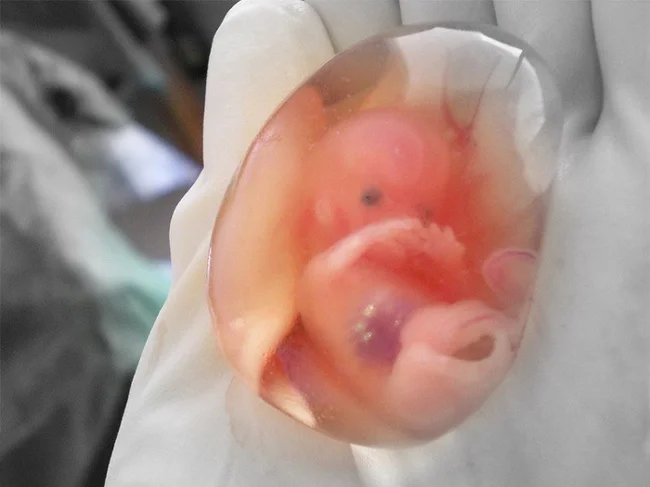

3. «От трети до половины всех оплодотворенных яйцеклеток не становятся жизнеспособной беременностью. Вместо этого они покидают тело под видом «обильной менструации». Большинство женщин даже не подозревают, что у них случился выкидыш».

8. «Женщины появляются на свет сразу со всеми яйцеклетками, которые они выпустят из яичников за свою жизнь. Следовательно, беременная женщина, вынашивающая ребенка женского пола, также вынашивает яйцеклетки, которые станут ее внуками».

22. «Если беременная женщина пострадала, стволовые клетки из ее матки переходят к поврежденным органам и восстанавливают их, чтобы защитить ребенка».